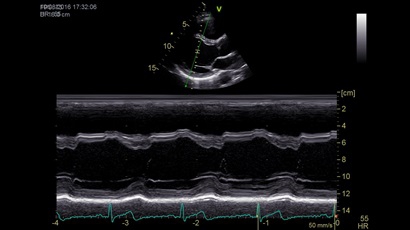

GE VIVID IQ - это передовая портативная система ультразвуковой диагностики, специально разработанная для обеспечения высокого качества образов и мобильности. Благодаря своим компактным размерам и легкому весу, VIVID IQ легко переносится и позволяет проводить УЗИ исследования в различных местах, включая комнаты пациентов, отделения скорой помощи и операционные.

GE VIVID IQ – это ультрасовременный, выполненный в виде ноутбука УЗИ сканер с самым передовым техническим оснащением для проведения диагностических обследований сердечно-сосудистой системы человека. Его особенно оценят бригады скорой помощи из-за малого веса всего 4,5 кг., удобства переноски, а также быстрого выхода из состояния сна для начала работ.

• Передовые технологии, такие как 4D чреспищеводная эхокардиография, ЭКГ, стресс-эхо, внутрисердечная ультразвуковая эхокардиография, тканевый доплер и другие.

• Режимы: 4D, 2D (B-режим), цветной допплеровский режим, режим энергетического допплера, M-режим, цветной M-режим, спектральные режимы импульсно-волнового допплера (PW) и непрерывно-волнового допплера (CW), визуализация скорости движения тканей.